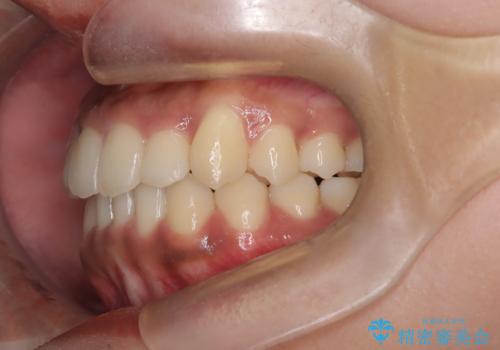

【インビザライン】笑ったときに目立つ八重歯をなおしたい

- 笑ったときに八重歯が見えることを主訴に来院されました。

下の前歯が一本足りない患者様でしたので、シミュレーションを作り、事前に患者様と治療ゴールのイメージをしっかり共有したうえでインビザラインを用いて治療を行っています。

奥歯を後ろのほうに動かすことで、前歯も少し下がることができ、矯正後の口元も満足していただきました。